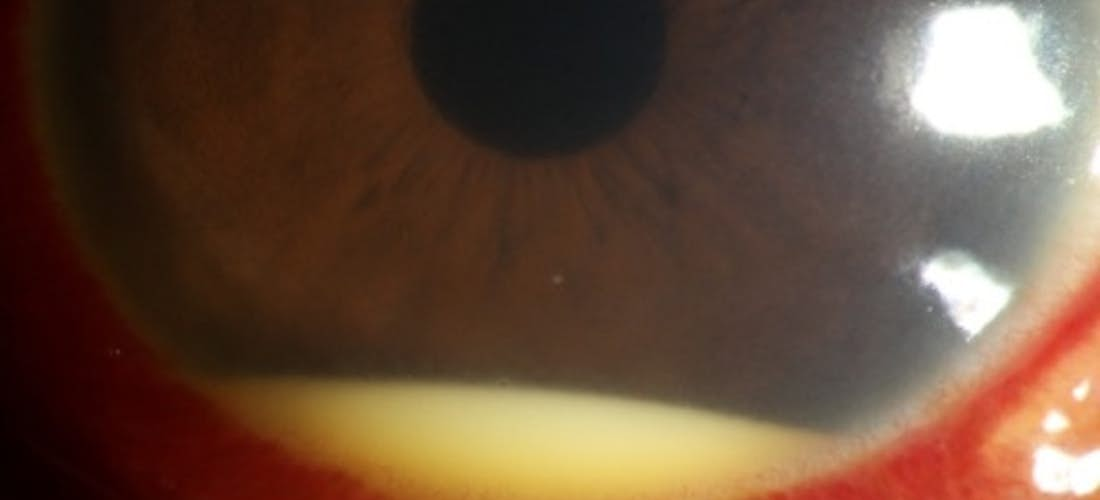

Cette vascularite touche le plus souvent les patients originaires du pourtour méditérrannéen, du Moyen Orient ou d'Asie. Elle se manifeste par des aphtes buccaux et génitaux, des lésions cutanées, des douleurs articulaires. Comme toutes les vascularites systémiques, elle peut se compliquer d’atteintes viscérales. L’atteinte ophtalmologique est une de ces complications et intéresse aussi bien les segments antérieur et postérieur de l’oeil.

Lorsque l’inflammation touche les gros vaisseaux (angio-Behçet), elle peut être responsable de thromboses artérielles ou veineuses ou encore d’anévrysmes artériels. L’atteinte neurologique (neuro-Behçet) survient souvent plus tardivement dans l’évolution de la maladie et peut prendre des aspects très variés mais dominés par les méningo-encéphalites. Elle est grave et, comme pour certaines atteintes ophtalmologiques, source d'un handicap fonctionnel parfois important.